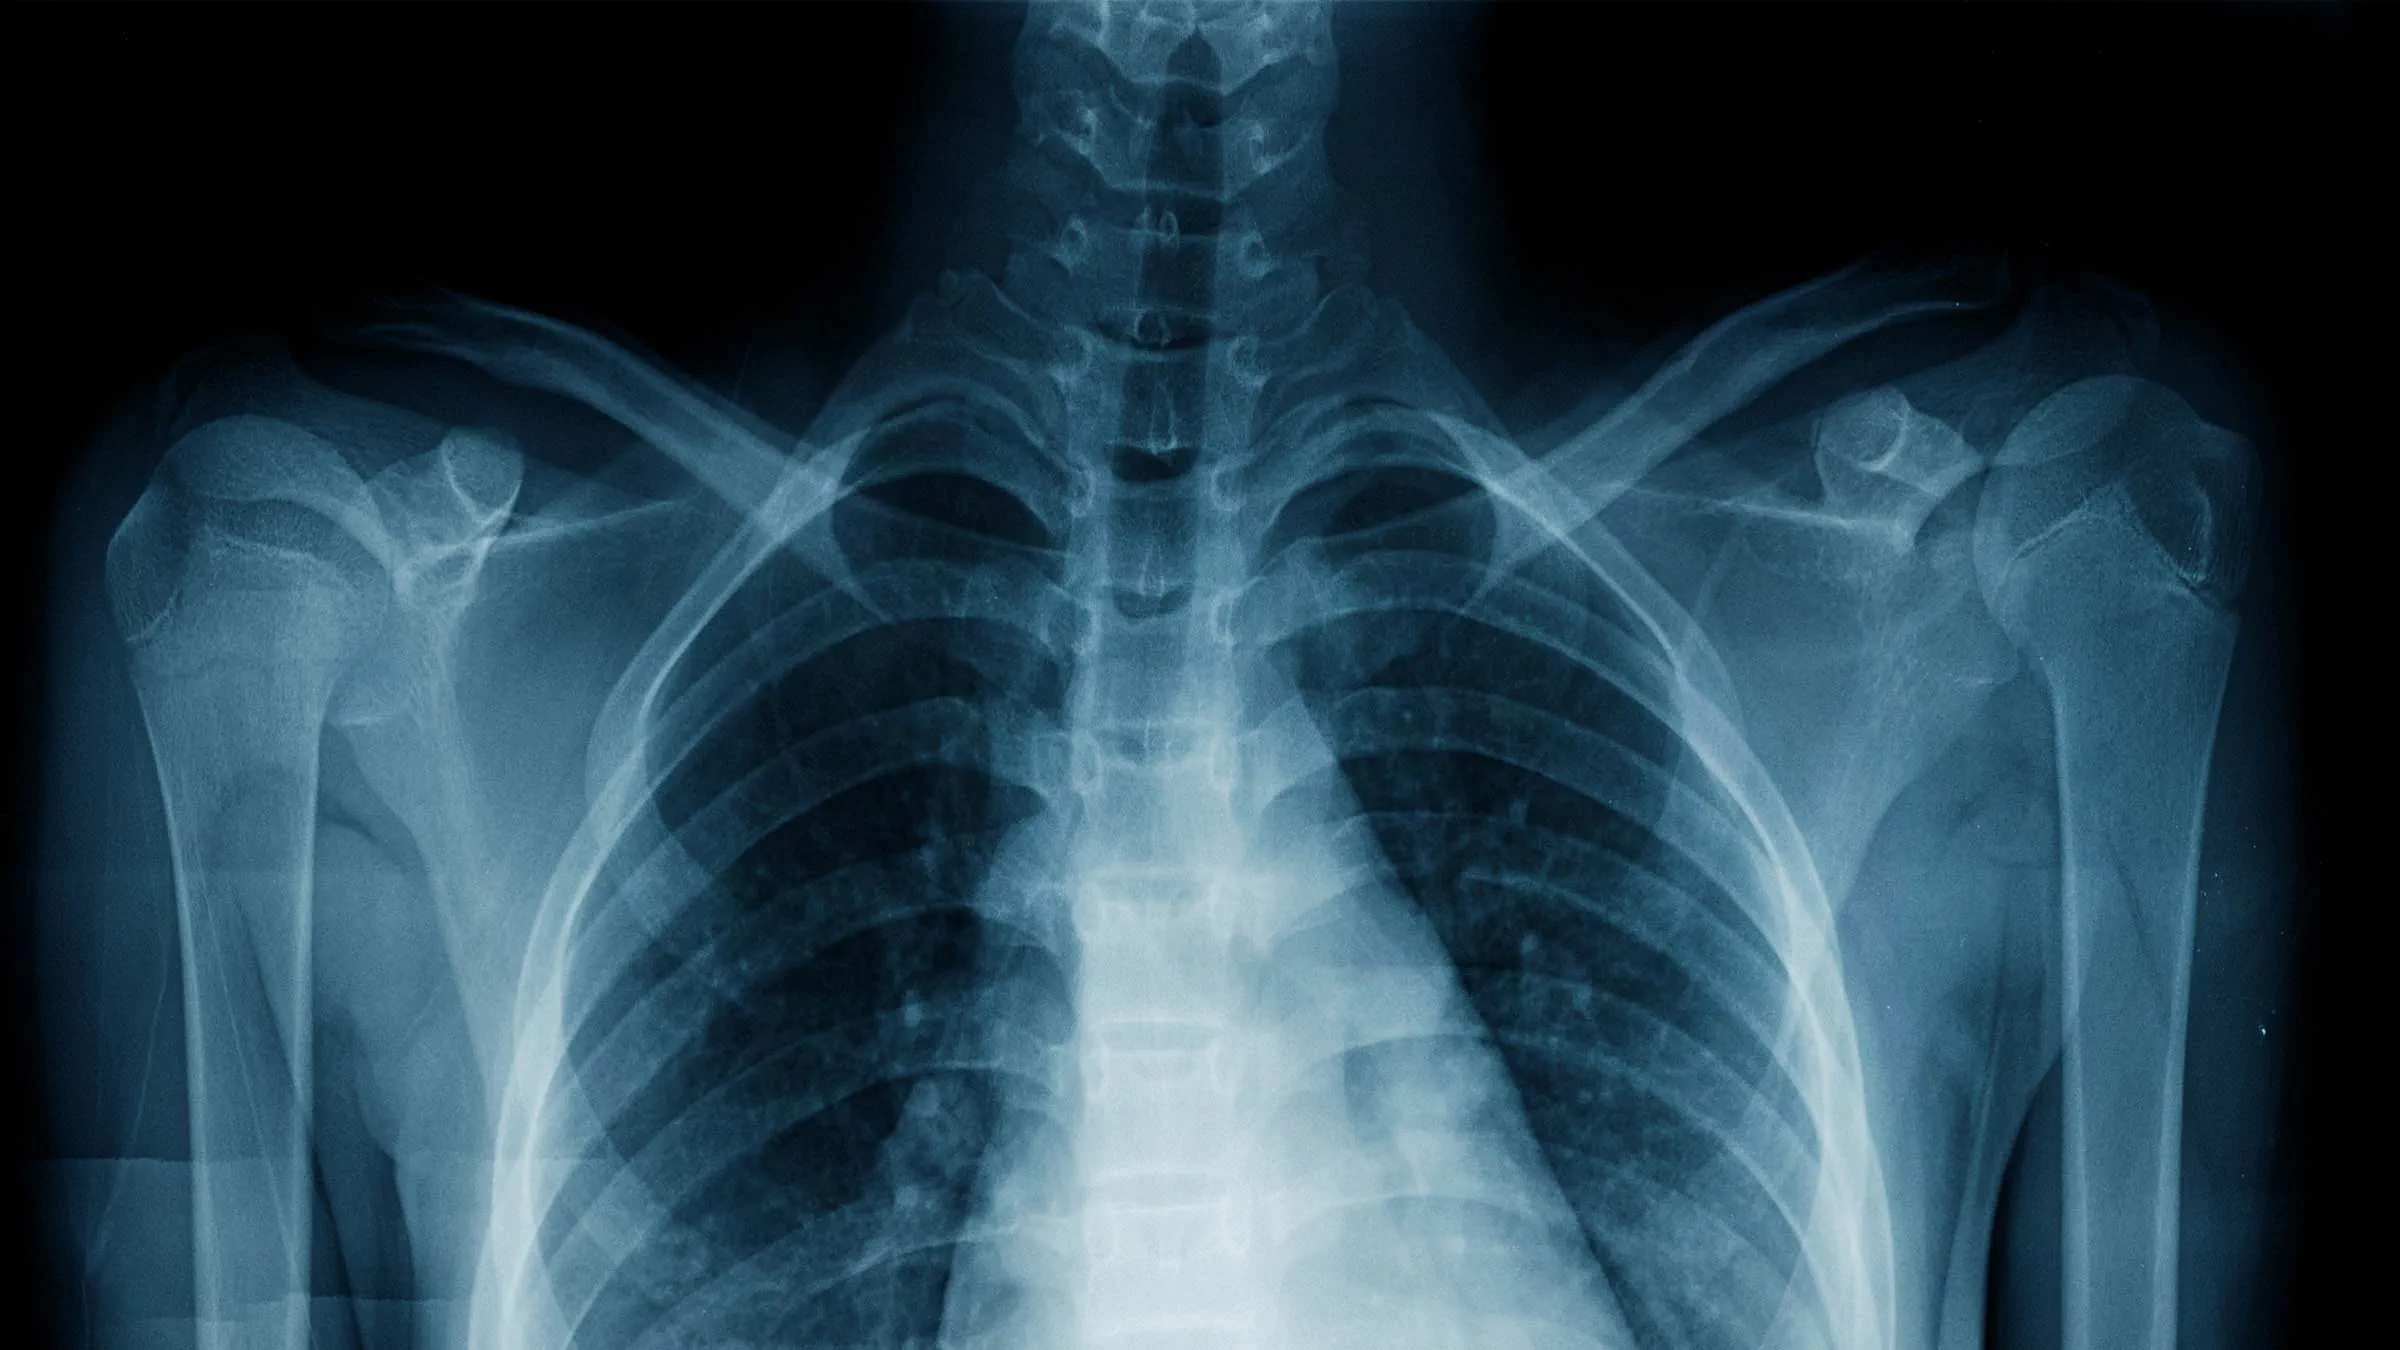

When it comes to healthcare, timely and accurate diagnostic imaging plays a vital role in determining the right treatment. At Innovative UCC, we specialize in offering precise and efficient diagnostic services for patients searching for Xray near me. Our state-of-the-art technology and expert technicians ensure you receive the most accurate imaging results, helping you and your doctor make informed decisions about your health. Whether you’ve sustained an injury, need a chest X-ray, or require a follow-up scan, our facility provides the perfect solution for those in need of Xray near me.

An Xray near me can help diagnose a wide range of medical conditions. These include broken bones, joint dislocations, lung infections, kidney stones, and even dental issues. At Innovative UCC, we use advanced digital imaging to ensure every detail is captured with clarity. Whether it’s a simple bone fracture or a complex chest condition, our Xray near me services are designed to provide the accuracy your doctor relies on. Patients trust us because we deliver dependable results quickly and professionally.

Our commitment to excellence in diagnostic imaging sets us apart. At Innovative UCC, we use the latest digital radiography systems for our Xray near me services. Digital X-rays provide sharper images, reduce radiation exposure, and deliver results faster than traditional film methods. This technology allows our physicians to interpret results accurately, ensuring precise diagnoses. When you search for Xray near me, you deserve the best equipment and expertise — and that’s exactly what we provide at our facility.